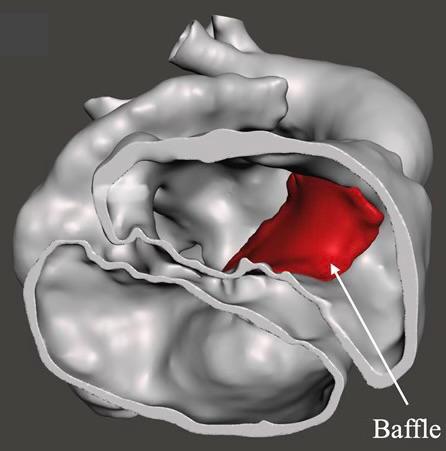

The printed model allows surgeons to examine internal details and anatomical relationships between the different parts of the heart with exceptional accuracy, including valve anatomy, the pathways of the major arteries, and the precise location of cardiac defects. This is reflected in improved outcomes during surgery.

In the treatment of congenital heart disease, 3D printing enables physicians to gain a highly accurate understanding of the patient’s complex cardiac anatomy by creating a three-dimensional model identical to the real heart. This helps cardiologists and surgeons plan the procedure in advance and choose the best approach for repairing the defects, increasing the chances of achieving a complete repair rather than resorting to palliative procedures that do not provide a definitive cure. The technology also contributes to better surgical outcomes, fewer complications, and an improved quality of life for patients in the long term.